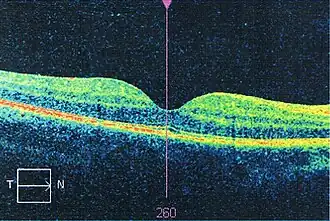

Koherencyjna tomografia optyczna jest jedną z wielu technik tomografii optycznej. Komercyjnie dostępne urządzenia mają różnorodne zastosowania, między innymi w procesie restauracji architektury czy diagnostyce medycznej, szczególnie w okulistyce do nieinwazyjnego badania oczu i uzyskiwania szczegółowych obrazów wnętrza siatkówki. Ostatnio koherencyjna tomografia optyczna zaczęła również być stosowana w kardiologii interwencyjnej jako sposób diagnozy choroby niedokrwiennej serca[1]. Wdrożenie koherentnych tomografów optycznych w domenie częstotliwości umożliwiło uzyskanie wyższego stosunku sygnału do szumu, pozwalając na szybszy odbiór sygnału.

Pierwsze obrazy OCT in vivo – pokazujące struktury siatkówki – zostały opublikowane w 1993[8][9]. OCT używane było też w różnych projektach konserwacji i restauracji dzieł sztuki m.in. do badania i analizy kolejnych warstw obrazów. OCT ma wiele zalet nad innymi technikami medycznego obrazowania.

Koherencyjna tomografia optyczna jest uznaną metodą obrazowania medycznego. Jest powszechnie używana do otrzymywania wysokiej jakości obrazów przednich części oka i siatkówki, co jest szybką metodą natychmiastowej diagnozy i oceny degeneracji aksonów u pacjenta ze stwardnieniem rozsianym[18] czy zwyrodnieniem plamki żółtej[19]. Badania wykazały, że OCT sprawdza się jako narzędzie do obserwowania postępowania jaskry. Badacze zajmują się też sposobem używania dziedziny częstotliwości OCT do obrazowania tętnic wieńcowych w celu wczesnego wykrycia chorób układu krwionośnego. Badacze używali także OCT aby uzyskać szczegółowe obrazy mózgów myszy za pomocą przejrzystego „okna” zrobionego z ditlenku cyrkonu wczepionego w czaszkę[20].